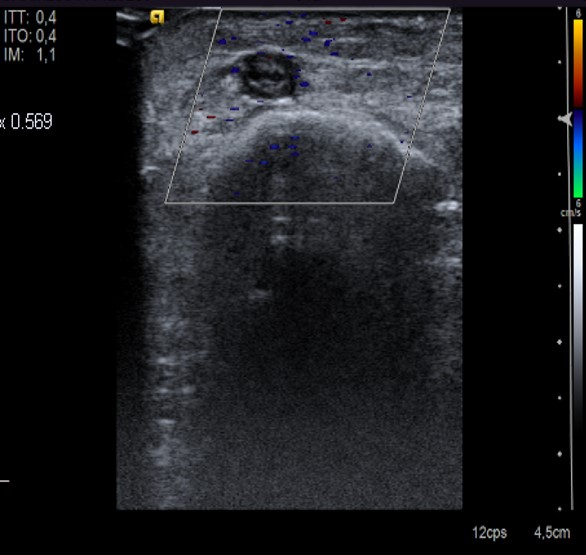

La Eco-Doppler de extremidades inferiores (ED) es una técnica no invasiva que ha demostrado su buena sensibilidad y especificidad en el diagnóstico de la TVP en comparación con la flebografía. Además, permite diagnosticar otras patologías que podrían justificar la clínica del paciente. Se debe hacer de urgencia siempre que sea posible.

Se consideran criterios diagnósticos de TVP: la presencia de material ecogénico intraluminal, la distensión venosa, con crecimiento significativo del tamaño vascular, o la existencia de circulación colateral, la imposibilidad de colapsar completamente la vena y la ausencia de flujo venoso espontáneo.